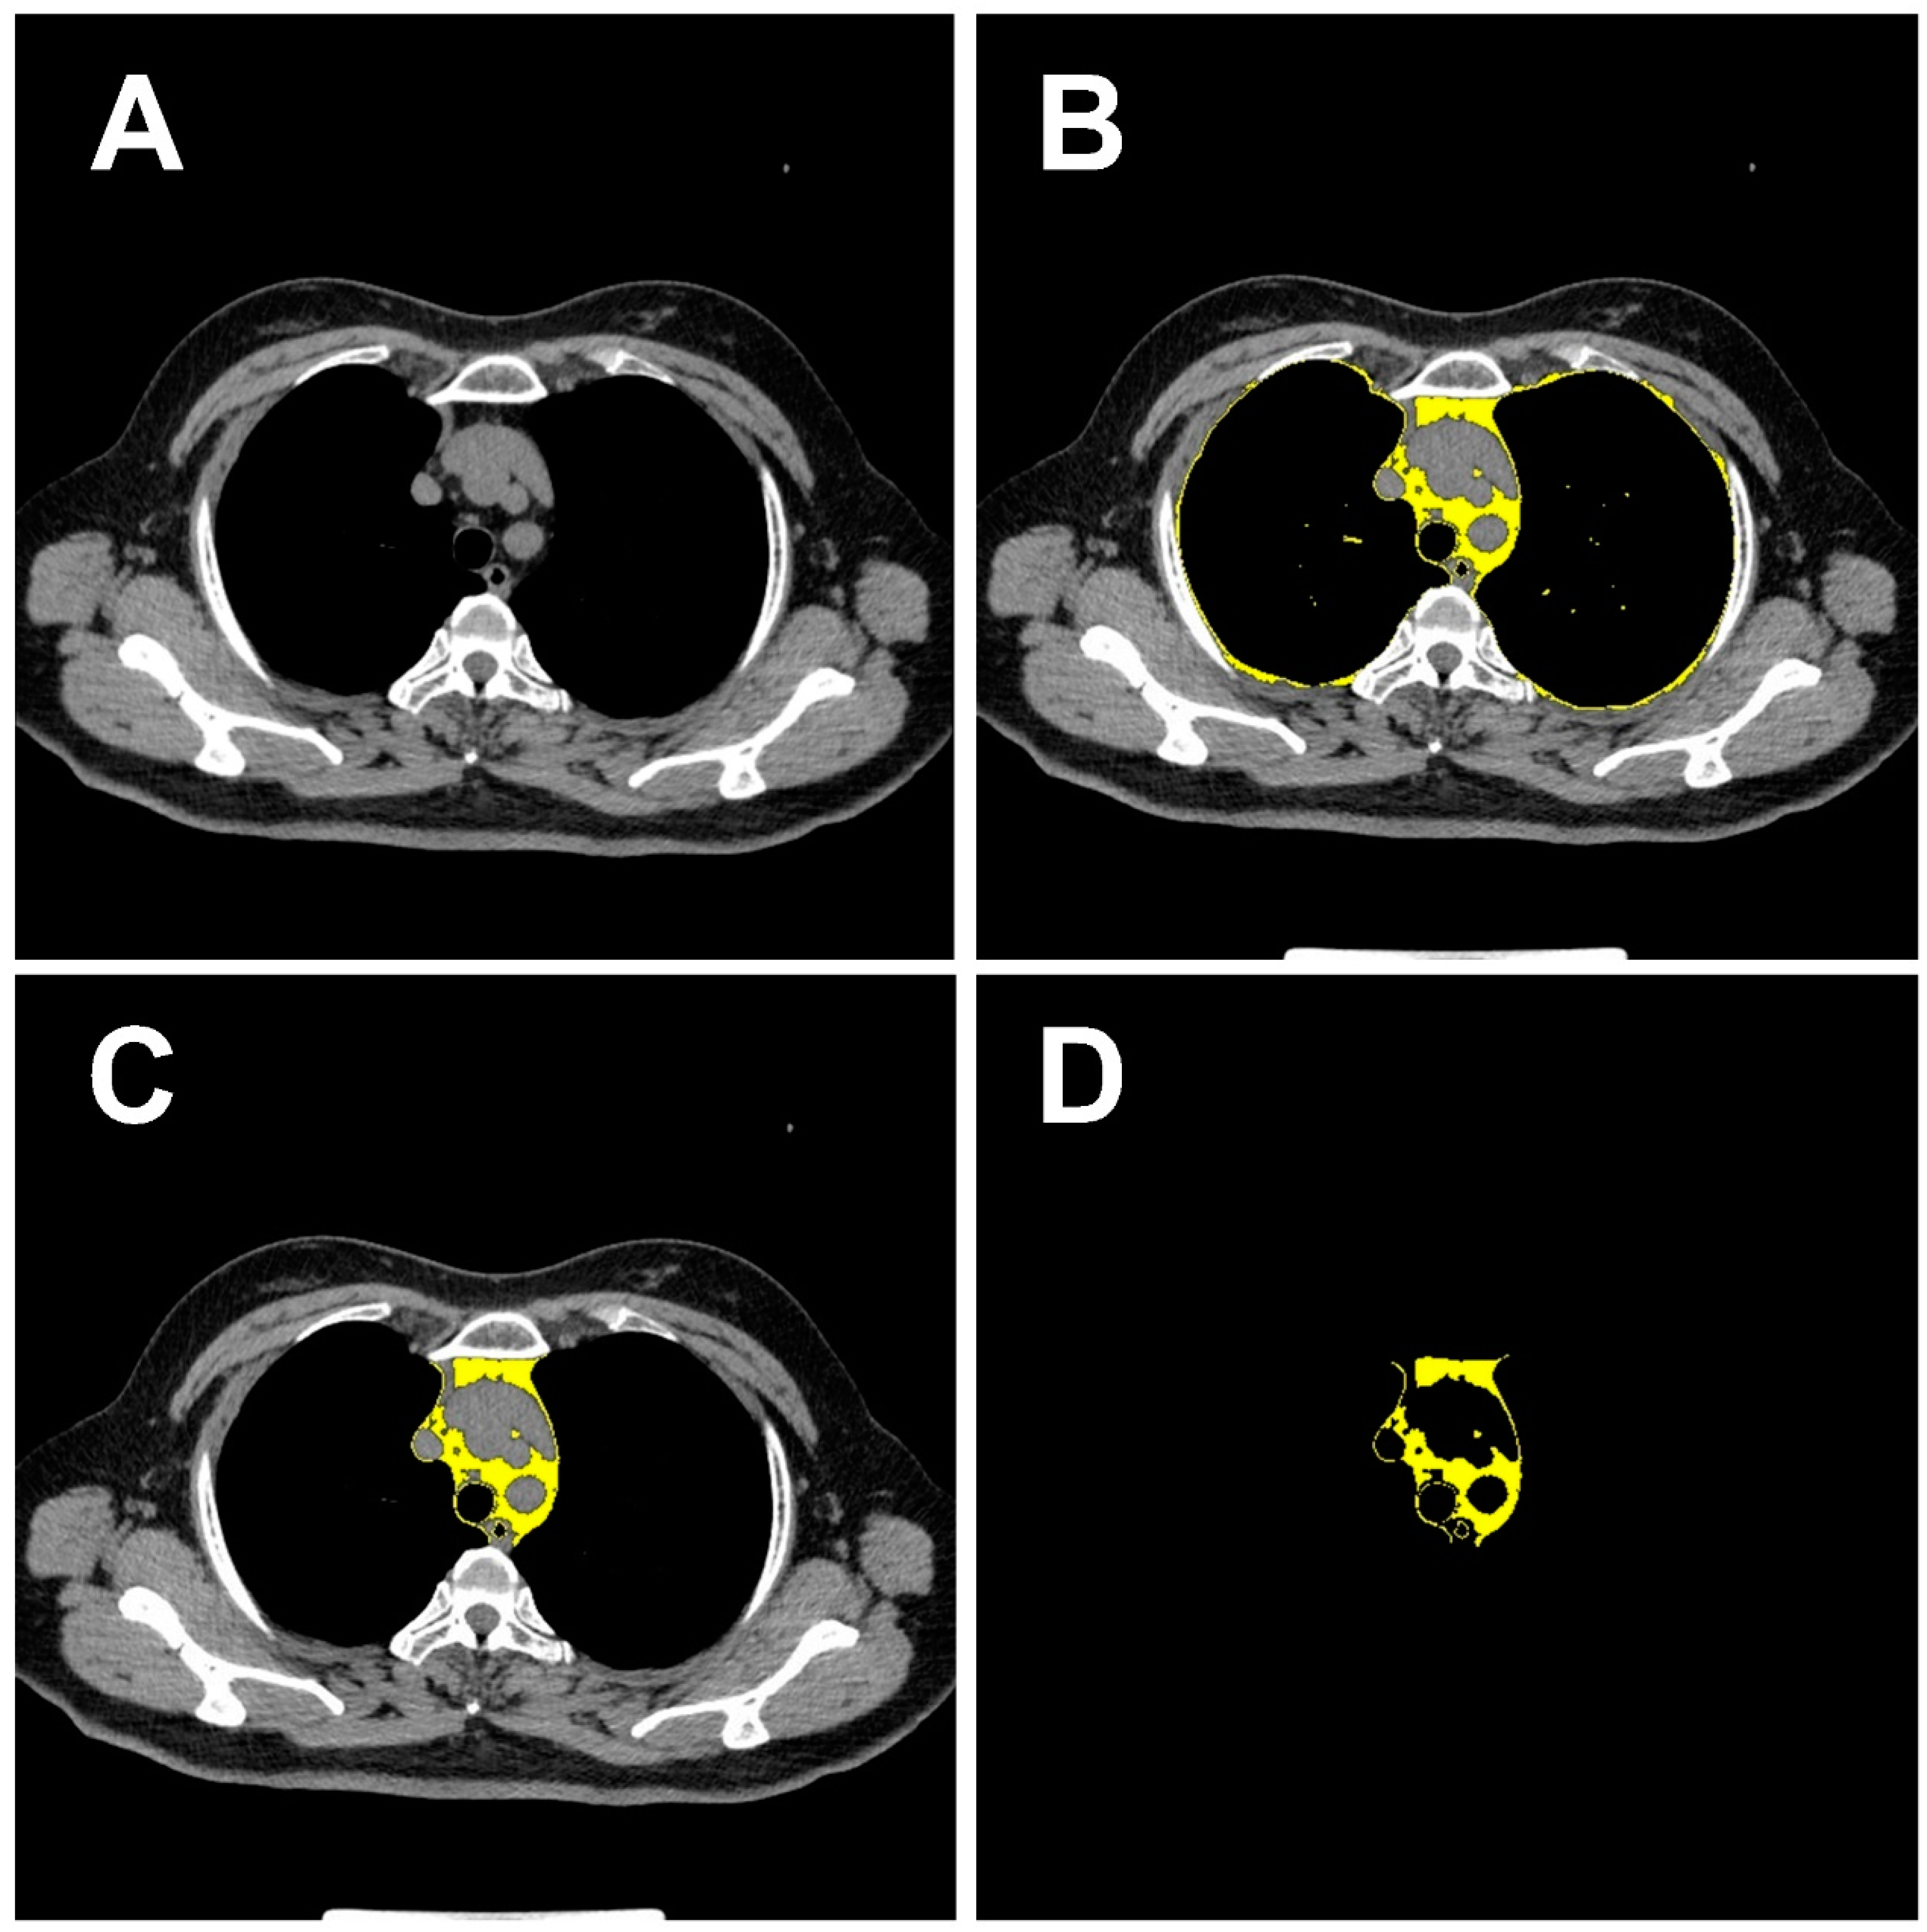

2.5. Deep Learning Feature Extraction of Pulmonary Nodules and Mediastinal Fat